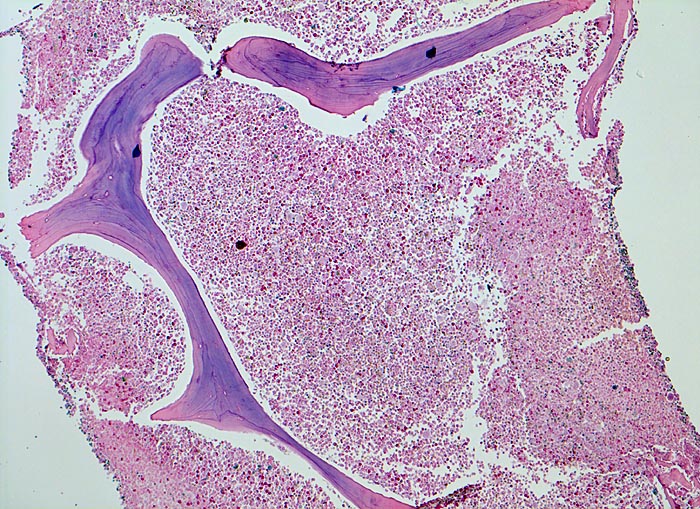

PathoPic – image database / PathoPic ID 3897 - chronische myeloische Leukämie (CML)

chronische myeloische Leukämie (CML)

Knochenmark, Beckenkamm

Vollständige Verdrängung von normalem blutbildendem Mark und Fettmark durch verschiedene Reifungsstufen der Myelopoese (buntes Bild). Zellularität gegen 100% (sogenanntes "packed marrow").

Müdigkeit und Gewichtsverlust. Ausgeprägte Leukozytose, Basophilie und leichte Anämie. Palpable Milz.

Das Verhältnis weisse zu roten Blutzellvorstufen liegt im normalen Knochenmark des Erwachsenen etwa bei 3:1, kann bei reaktiven Veränderungen aber stark verschoben sein. Die Zellularität ist altersabhängig. Als grobe Faustregel kann man davon ausgehen, dass das Knochenmark bei einem Kind fast 100% blutbildendes Mark enthält. Pro Jahrzehnt wird etwa 10% des blutbildenden Marks in Fettmark umgewandelt. Ein 50 jähriger hat somit ein etwa ausgeglichenes Verhältnis von blutbildendem Mark zu Fettmark.